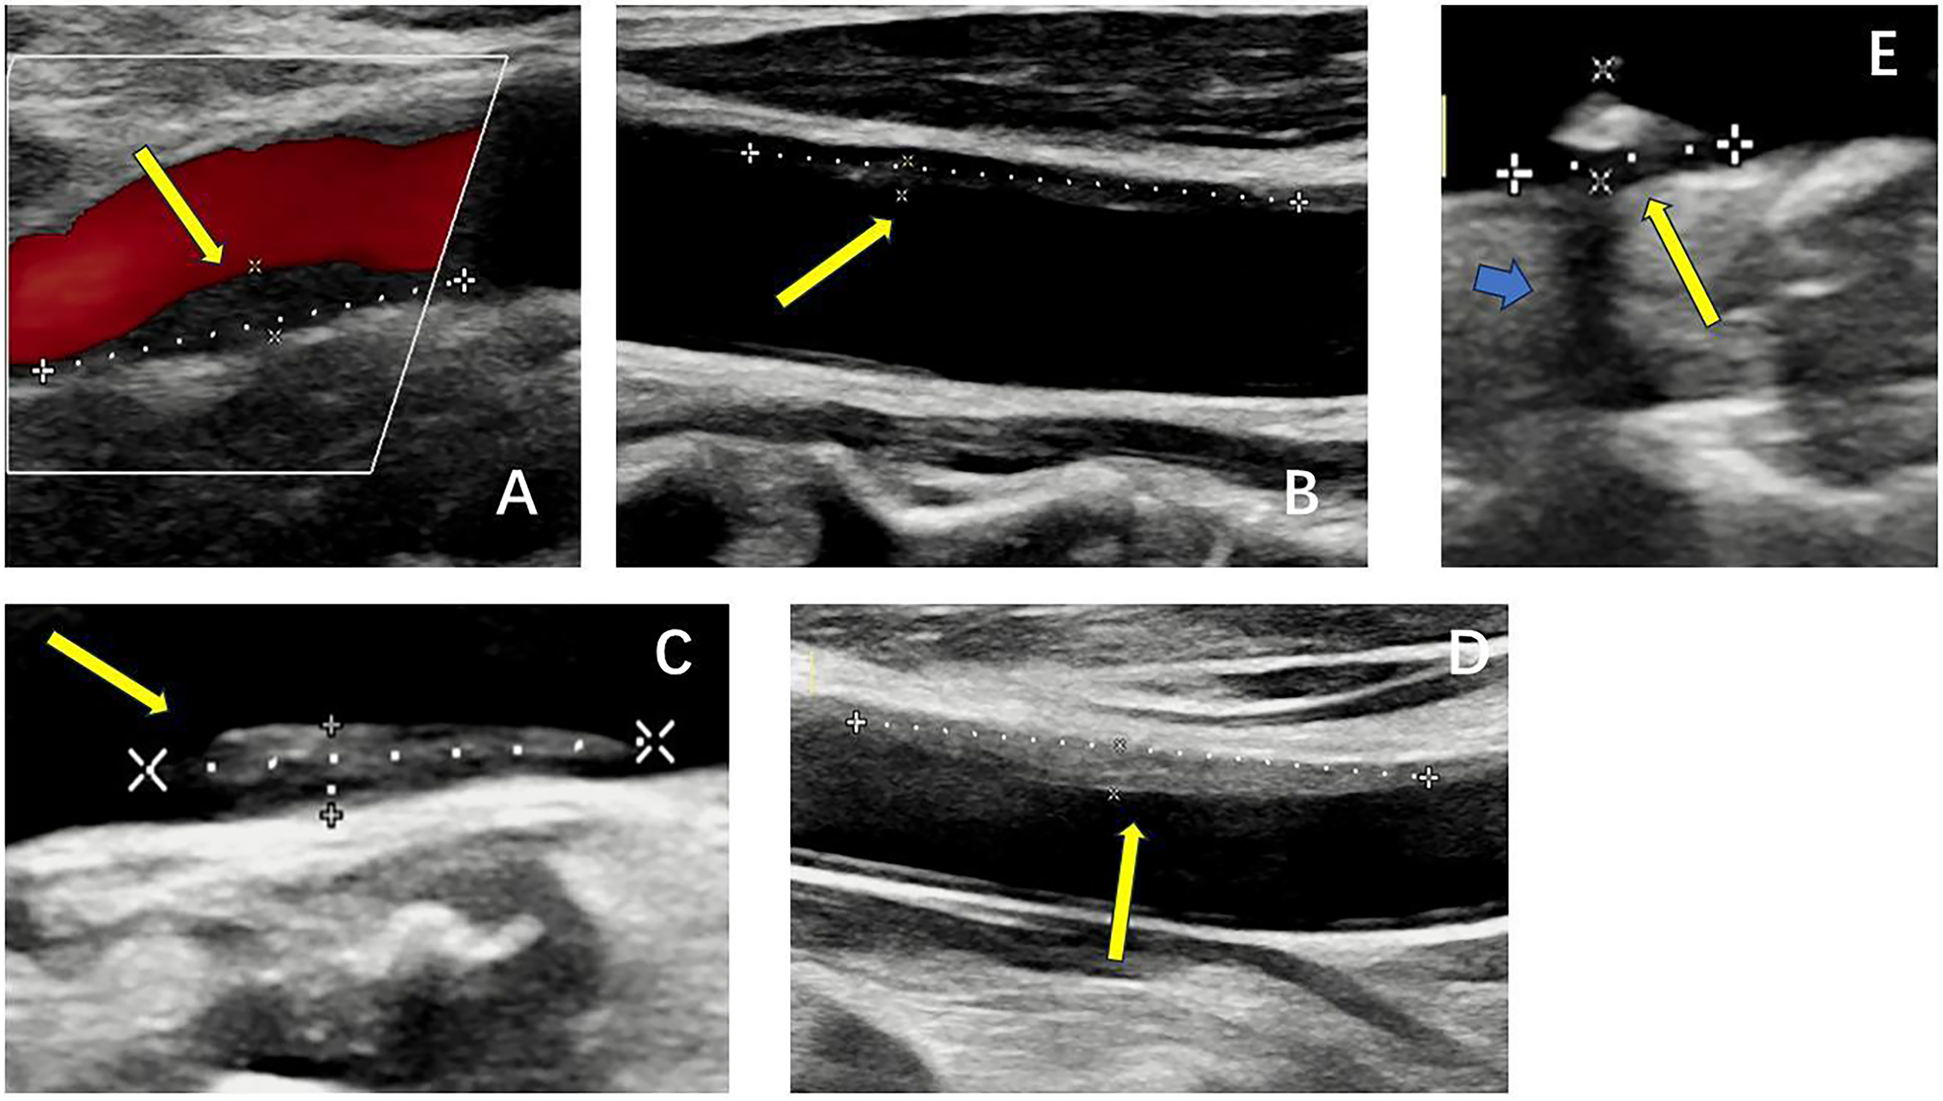

Real-time ultrasound (B-Mode, 2D Mode) is the primary imaging modality for initial assessment that can diagnose artery stenosis, as well as identify and locate plaque (25). With Doppler, color flow mode, it provides information on flow velocity, stenosis severity, and plaque surface and composition. There is an ultrasound-based classification, called Gray-Weale–Nicolaides (GWN) classification, distinguishing between five types (classes) of plaques, that is, uniformly echolucent plaque, predominately echolucent plaque, predominantly echogenic plaque, uniformly echogenic plaque, heavy calcification (26). (Figure 2) In addition, carotid intima-media thickness (IMT) is a quantitative parameter measured using high-resolution B-mode ultrasound, which is implicated in cardiovascular risk assessment. (Figure 3) IMT is more considered a surrogate marker of atherosclerosis, and yet its importance is rather debatable (27, 28). Also, considering the asynchronous movement of the plaque from B-mode ultrasound associated with a higher risk of stroke, Golemati S, et al. (29) statistically analyzed 135 plaques in 77 patients (59 men, 18 women) with carotid atherosclerosis and proved the ability to obtain tissue kinematic characteristics. It can be utilized to develop ultrasound-based risk stratification.

Figure 2

B-mode ultrasound images of five types of plaques distinguished by the gray-weale–nicolaides (GWN) classification including (A) uniformly echolucent plaque, (B) predominately echolucent plaque, (C) predominantly echogenic plaque, (D) uniformly echogenic plaque, and (E) heavy calcification. The yellow arrows indicate plaques. The blue arrow indicates the shadow.